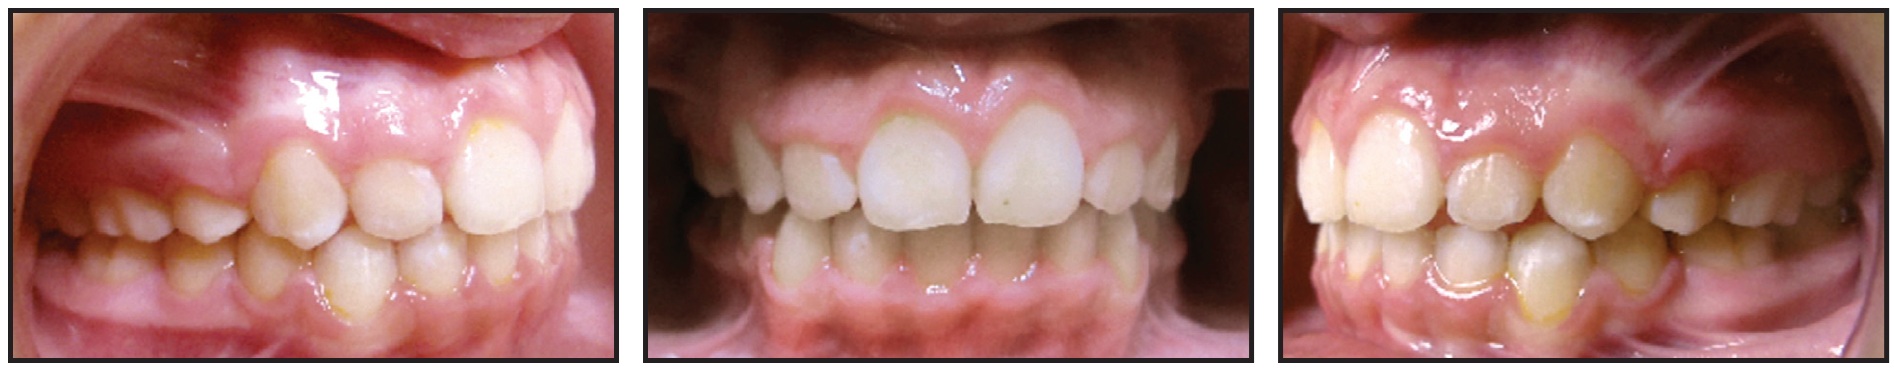

In this case, a 21-year-old female presented with a Class I malocclusion, excessive overjet, deep overbite, severe crowding, and bimaxillary protrusion (Fig. 8).

Fig. 8 21-year-old female patient with Class I malocclusion, excessive overjet, deep overbite, severe crowding, and bimaxillary protrusion before treatment.

We planned four premolar extractions, maximum anchorage, leveling of the curve of Spee, and incisor retraction. In the initial treatment design, I made the mistake of not adding attachments to the lower lateral incisors (Fig. 9).

Fig. 9 After 11 months of treatment and initial set of aligners, showing inadequate torque control of lower incisors and posterior open bite.

For the refinement stage, I focused on final space closure, root parallelism at the extraction sites, and finishing of the occlusion to close the posterior open bite. Although I added attachments to the lower lateral incisors for the refinement, the overall distal root angulation as designed and expressed in treatment was insufficient (Fig. 10). (The situation was exacerbated when one of the attachments debonded.)

Fig. 10 After one year of refinement, showing insufficient distal root angulation of lower incisors.

Regular monitoring of any orthodontic treatment is of paramount importance. Periodic assessments allow timely adjustments and interventions, ensuring proper root control. Before ordering additional aligners, I recommend that the appropriate root angulation be confirmed with a progress panoramic radiograph. Consider adding new attachments and distal root angulation in the digital setup if the issue persists or if you missed it in the initial treatment design. Such adjuncts to treatment can be applied in any challenging cases, including fixed segmental mechanics.